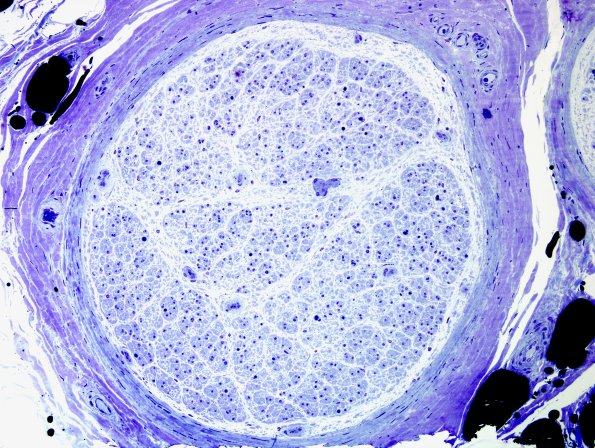

Washington University Experience | PERIPHERAL NEUROPATHY | 4 AXONAL DEGENERATION | 2 Plastic Sections | 14A1 Axonal degeneration (end-stage nerve, Case 14) Plastic 4

Essentially there are no remaining axons in this end stage nerve of a 71-year-old male with muscle weakness and numbness in all four distal extremities thought to have mononeuritis multiplex (by EMG/NCS) associated with rheumatoid arthritis. ---- 14A1,2 There are only a few small myelinated axons remaining in this fascicle.